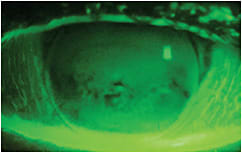

A 54-year-old monocular patient who had aphakia OS reported with corneal GP lens fit issues. His current contact lens was inferiorly decentered and was binding to his cornea without movement (Figures 2 and 3).